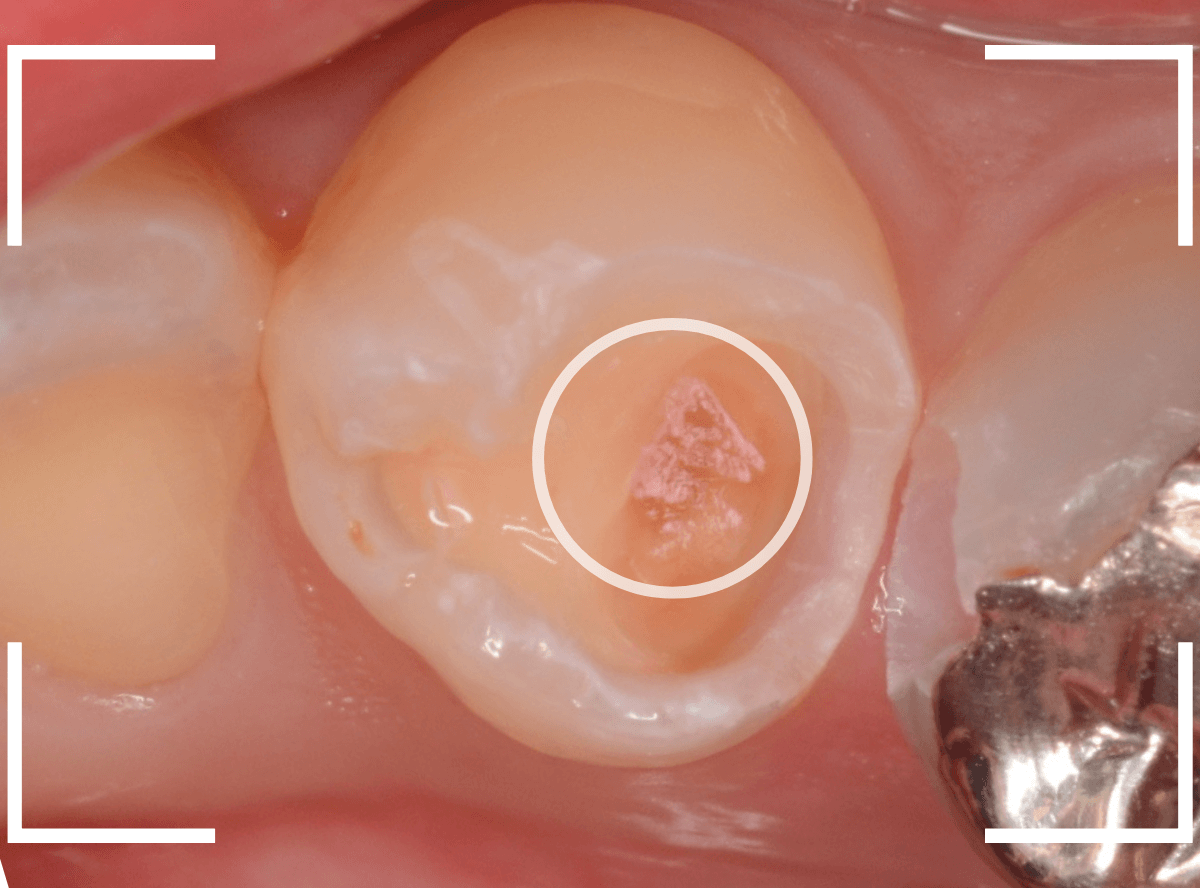

Case.24 レジンの下で虫歯が進行

上の奥歯の虫歯が見つかった患者さんです。

初診のチェックの際に、上から目視すると、レジンがつめてある〇部分が薄暗く黒くなっているので、これは虫歯があるな、とわかりました。

レントゲン写真で確認します。

先ほどの〇部分は明らかな虫歯になっているのがわかります。

この辺りはレジンがつめてありますが、その下もうっすらと虫歯になっていそうです。

先ほどの黒く見えた部分は少し削るとすぐに虫歯が出てきました。

思ったよりも深めの虫歯ですね。

レジンの中も全体にうっすらと虫歯になっていました。

このくらいの虫歯でも、患者さんは自覚症状はありませんでした。

ご自身の自覚症状だけでは、虫歯の状況がわからないですし、自然に虫歯が治る事もありません。

いつものお話ですが、定期的なメンテナンスで、虫歯の早期発見・治療を心がけましょう。